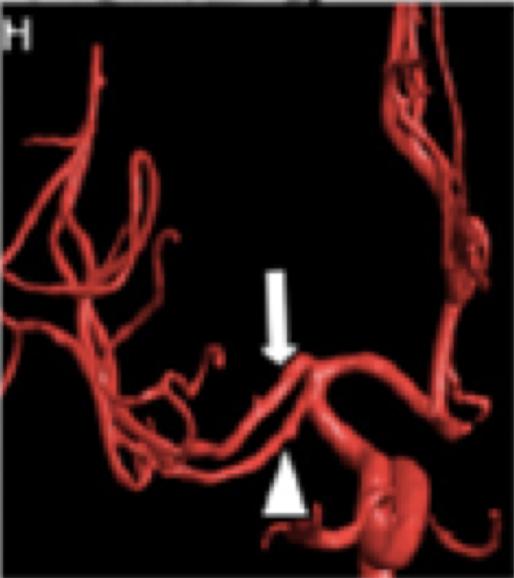

4周后患者拟进一步行颈动脉支架置入术。然而,术中进行的诊断性血管造影显示:颈动脉夹层几乎完全消失,未见明显的官腔狭窄以及内膜瓣(图1G)。右侧颈动脉球水平可见呈喙状的一个微小突起(图1G),可能是此前夹层的残留。因此,该患者最终未行支架置入。三维旋转血管造影显示AMCA双支完全再通(图1H)。3个月后随访,该患者的改良Rankin评分为0分。